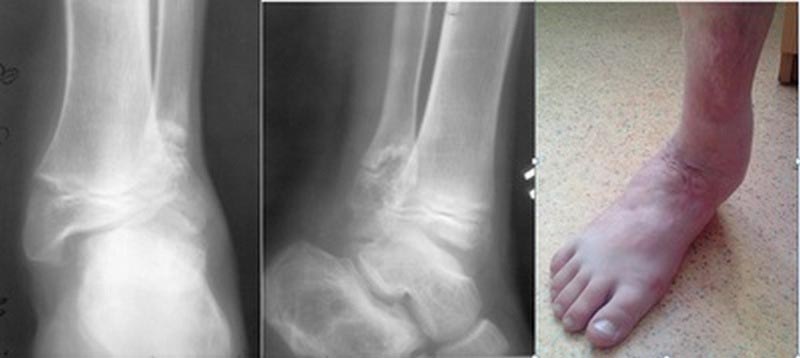

Посттравматическая деформация (нестабильность) голеностопного сустава у ребёнка 13 лет.

6 лет после ДТП. Жалобы на сильную боль при ходьбе . Разрушена вилка сустава, за счет деформации и укорочения наружной лодыжки . Поэтому стопа уходит в вальгус . Артродез не вариант - ребенок растет .